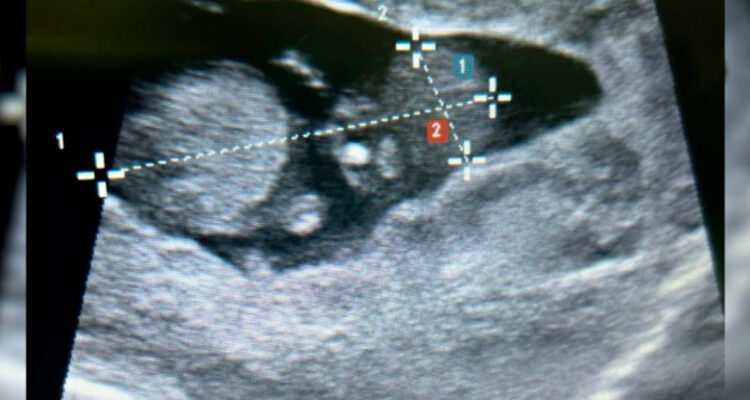

El doctor Jorge Jericó Araujo, cirujano del Servicio de Cirugía, relató que la mujer “ingresó al tópico de ginecología de emergencia con antecedentes de dos cirugías previas realizadas en otro establecimiento por un supuesto embarazo ectópico. Tras exámenes de imagen, se descubrió que el embrión seguía en su cuerpo”.

Tras esto, la cirugía reveló que portaba un embrión de seis semanas implantado en el tejido hepático, que los médicos extrajeron cuidadosamente.